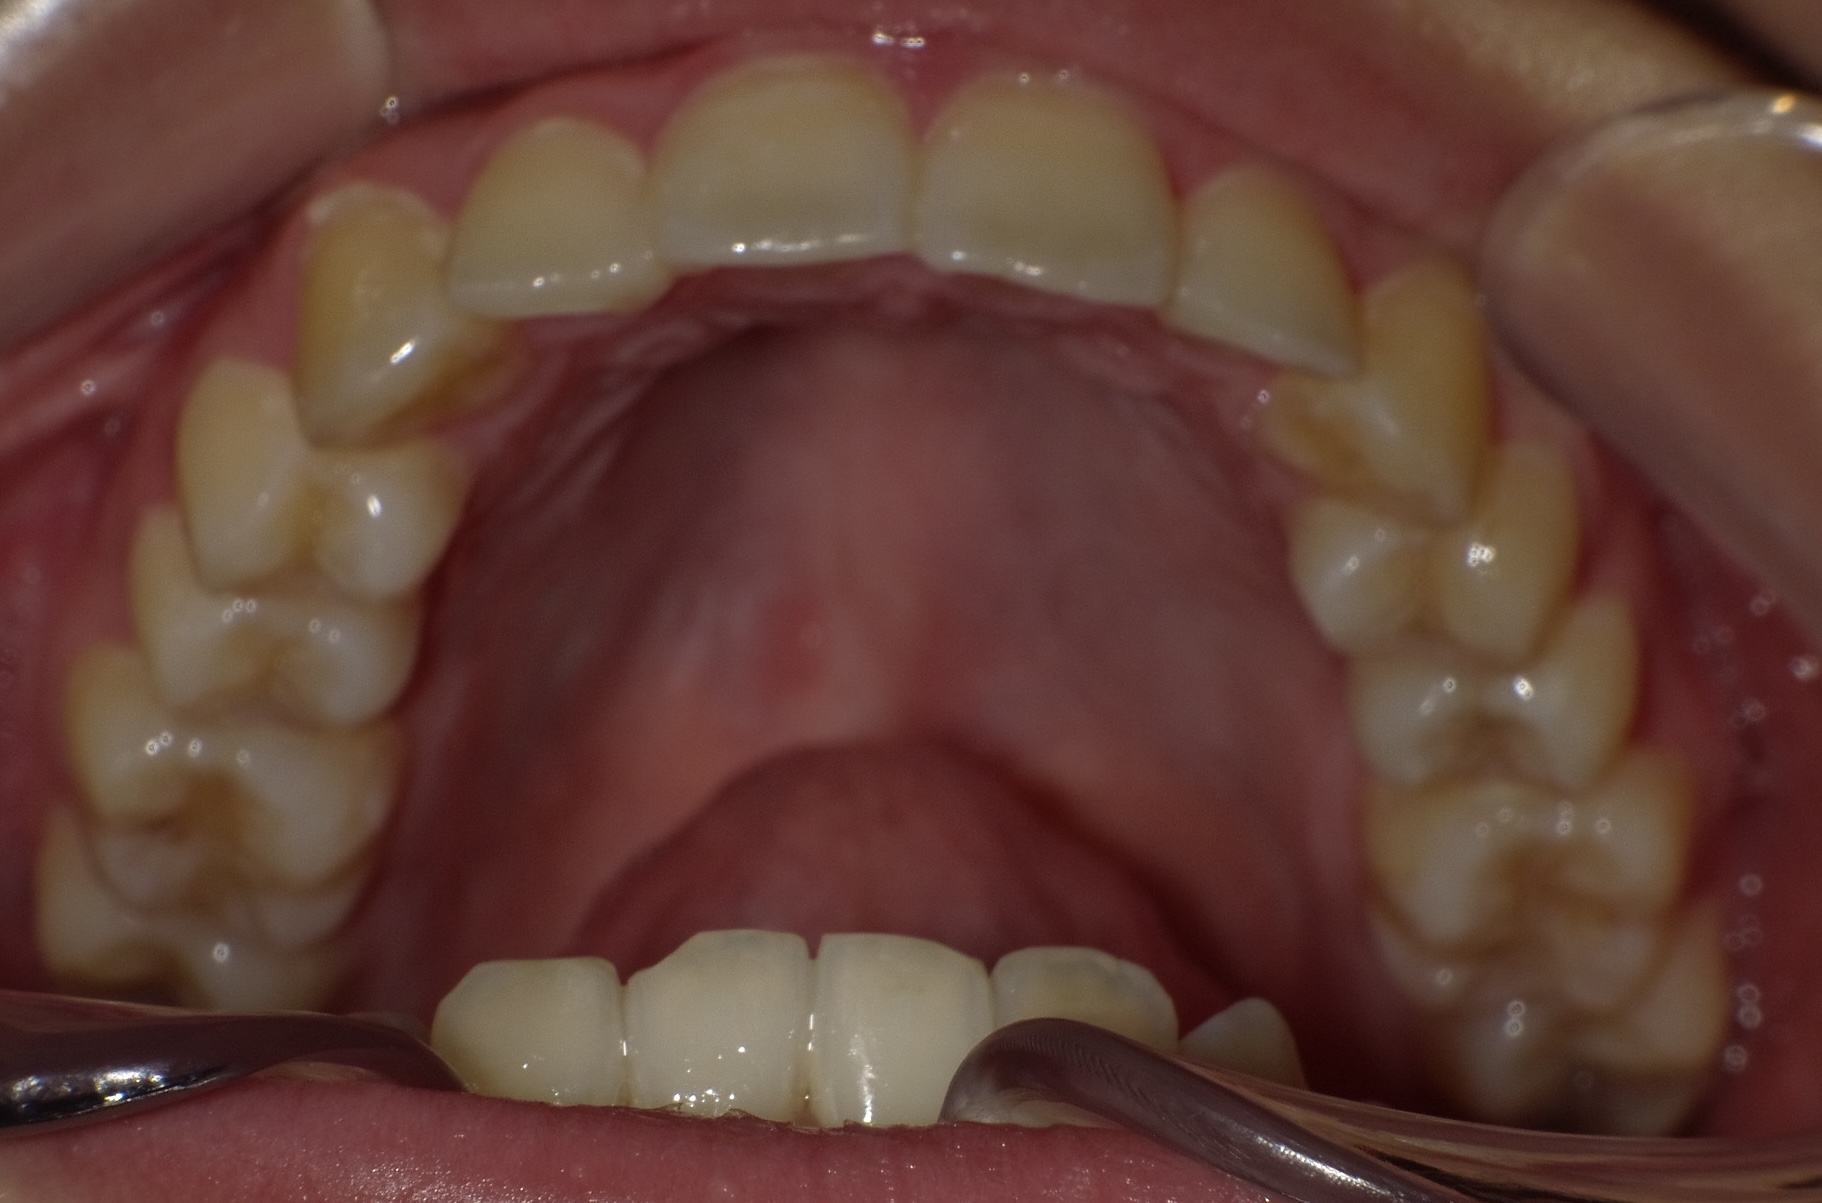

矯正前

途中経過

矯正後